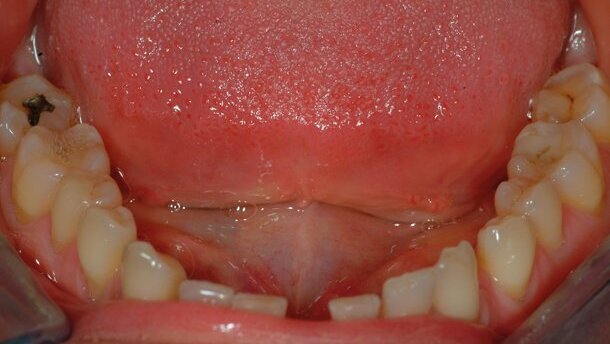

Gli interventi terapeutici sono diventati sempre più sofisticati e complessi con la necessità di una stretta collaborazione tra le diverse discipline dell’odontoiatria3. L’ortodonzia rappresenta sicuramente una tra le discipline guida in questo ambito: la ricerca tecnica e metodologica dei diversi sistemi di trattamento ortodontico ha portato infatti in questi ultimi anni a un notevole ampliamento delle possibilità terapeutiche, creando nuovi sviluppi per quanto riguarda nosologia, protocolli terapeutici e applicazioni strumentali a livello interdisciplinare in particolare nei soggetti fine crescita4-8.

Coniugare salute del cavo orale ed estetica del sorriso è una grande sfida per il team odontoiatrico. Erogare approcci clinici personalizzati e minimamente...